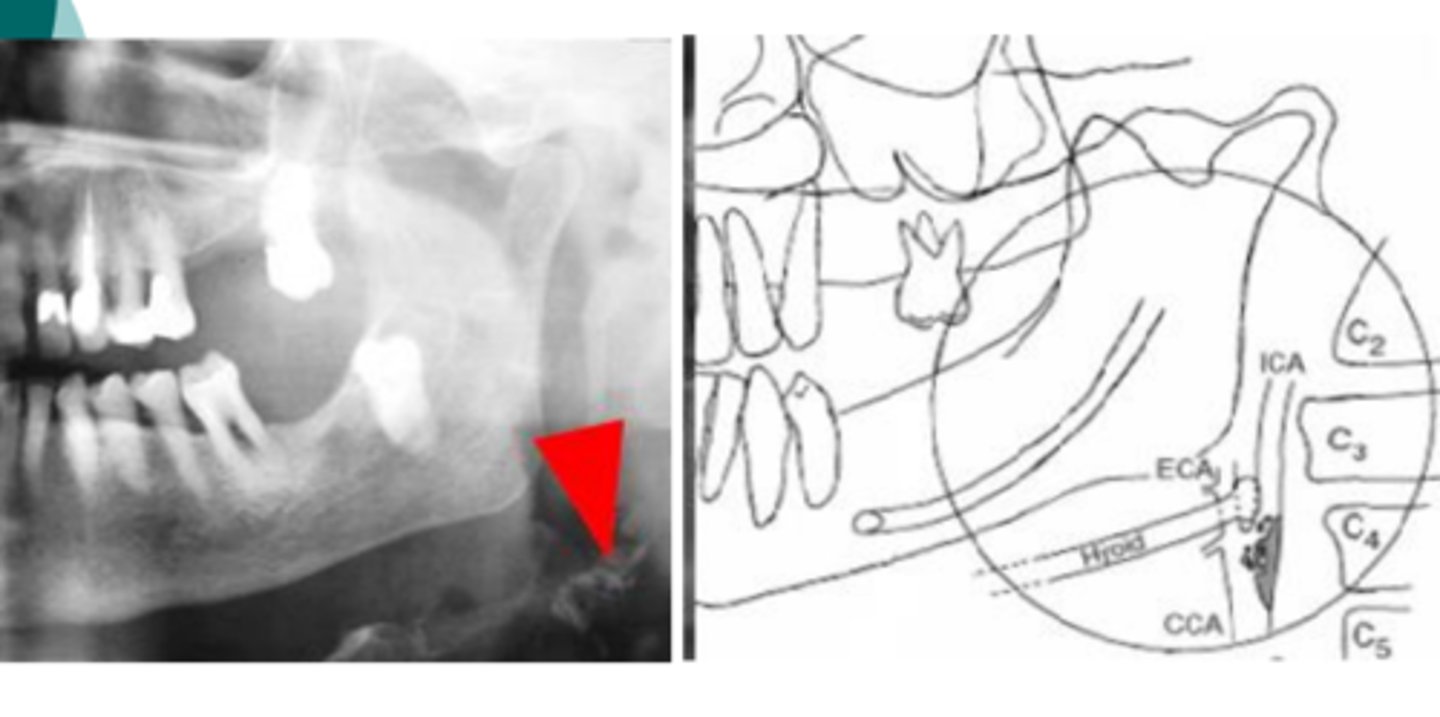

What is indicated by calcified atheroma's at the bifurcation?

Common carotid artery